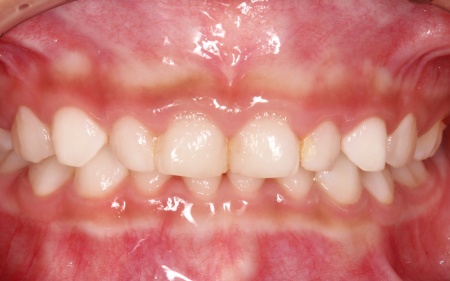

治療前

診断結果 拝見したところ、乳歯が隙間なく密集して生えている状態でした。

通常、乳歯の時期には歯と歯の間に発育空隙(はついくくうげき)と呼ばれる自然な隙間や、犬歯の前後に霊長空隙(れいちょうくうげき)と呼ばれる特徴的な隙間があります。

この隙間は、将来永久歯が生えるために必要なスペースを確保するためのものです。

しかし、患者様はこれらの重要な隙間がほとんど見られませんでした。

今のままでは、今後永久歯が適切な位置に並ぶためのスペースが不足すると考えられます。